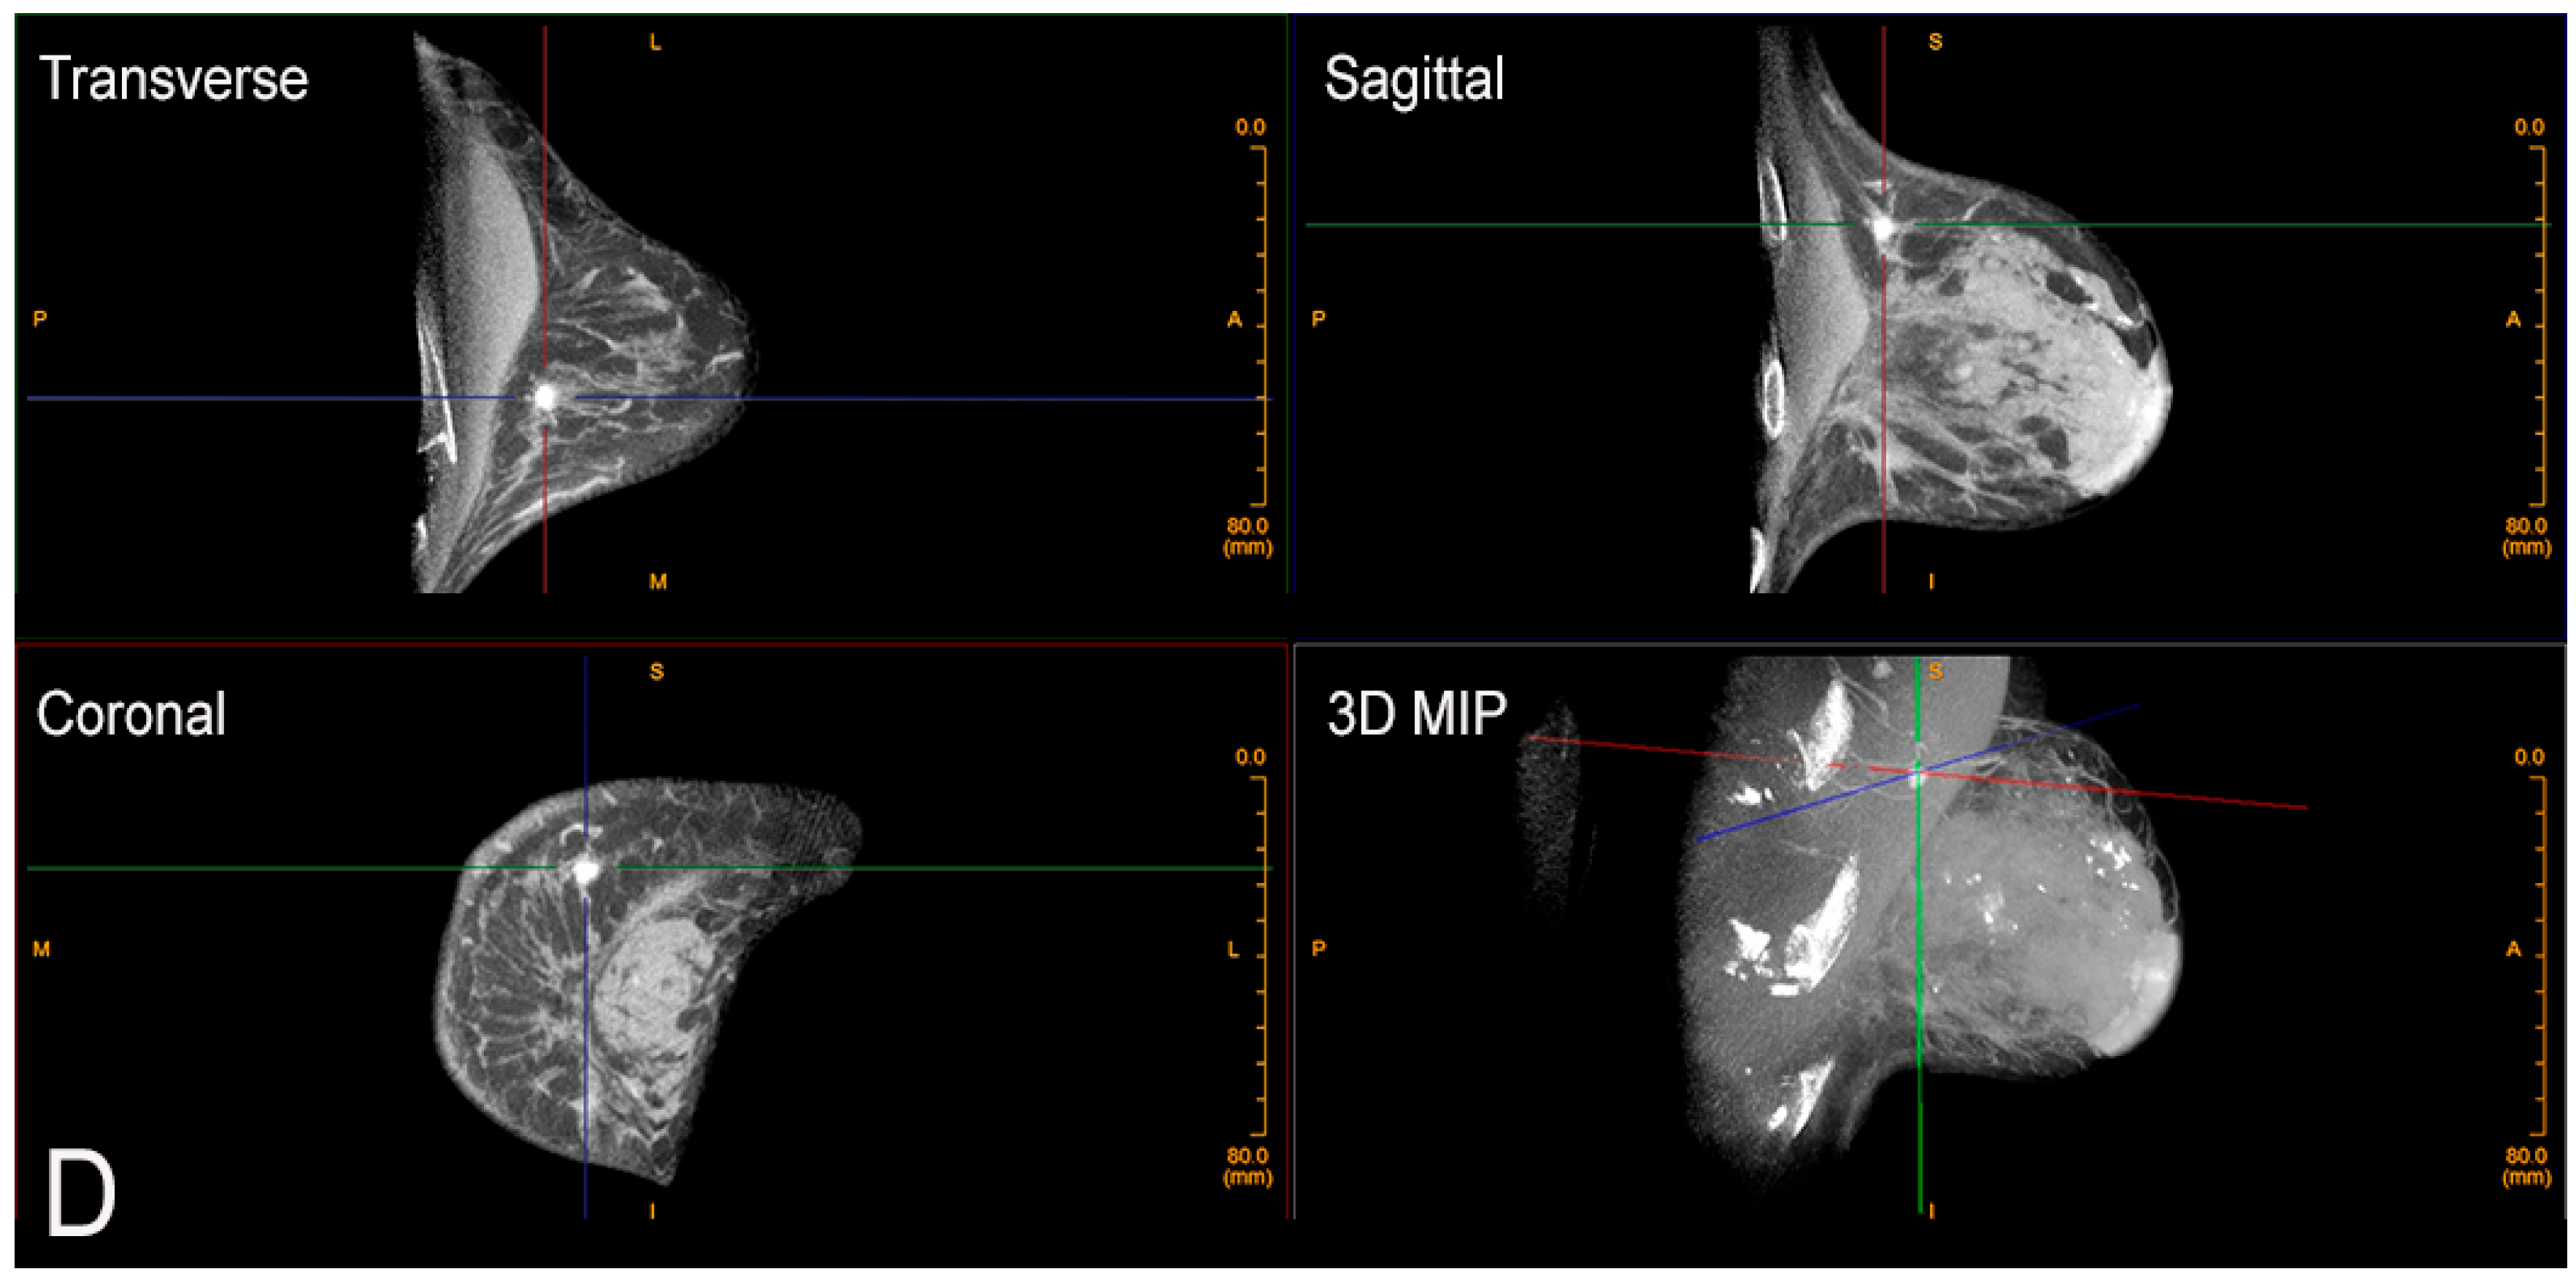

Figure 1.

Limitation of mammography for dense breasts. Bilateral craniocaudal (CC) (A) and bilateral mediolateral oblique (MLO) (B) mammograms showing extremely dense breasts (ACR density category d) [7]. The mammogram is negative (Breast Imaging Reporting and Data System (BI-RADS) 1). (C) Fortunately, the patient had a screening ultrasound shortly thereafter showing a 1 cm cancer at the 10 o’clock position in the right breast. The mammogram was a false negative. The patient came to no harm since the ultrasound was performed within a short period of time. The cancer was grade I invasive ductal carcinoma with negative nodes. Survival after treatment is near 100% [8].